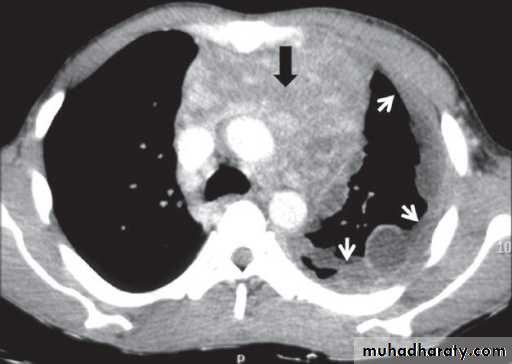

CXR & CT: it appears as a small well circumscribed mass or a bulky lobulated mass confluent with adjacent mediastinal structures

Imaging including CXR, CT, MRI.